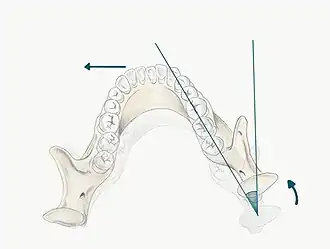

The maxilla forms a crucial aspect of the upper facial skeleton. Two irregularly shaped bones fuse at the intermaxillary suture during development forming the upper jaw. This forms the palate of the oral cavity and also supports the alveolar ridges that hold the upper teeth in place.[3] The lower facial skeleton on the other hand, is formed of the mandible, a U-shaped bone, which supports the lower teeth and also forms part of the TMJ. The mandibular condyle and the squamous portion of the temporal bone, at the base of the cranium articulate with one another.[4]

In order to fully understand the development of occlusion and malocclusion, it is important to understand the premolar dynamics in the mixed dentition stage. The mixed dentition stage is when both primary and permanent teeth are present. The permanent premolars erupt ~9–12 years of age, replacing the primary molars. The erupting premolars are smaller than the teeth they are replacing and this difference in space between the primary molars and their successors (1.5mm for maxillary, 2.5mm for mandibular[7]), termed Leeway Space. This allows the permanent molars to drift mesially into the spaces and develop a Class I occlusion.

When discussing the occlusion of the posterior teeth, the classification refers to the first molars and may be divided into three categories:

- Class I: The mandibular first molar occludes mesially to the maxillary first molar, with the mesiobuccal cusp of maxillary first molar occluding in the buccal groove of mandibular first molar

- Class II: The mesiobuccal cusp of the maxillary first molar occludes anterior to the buccal groove of the mandibular first molar

- Class III: If the mesiobuccal cusp of the maxillary first molar occludes posterior to the buccal groove of the mandibular first molar[8]